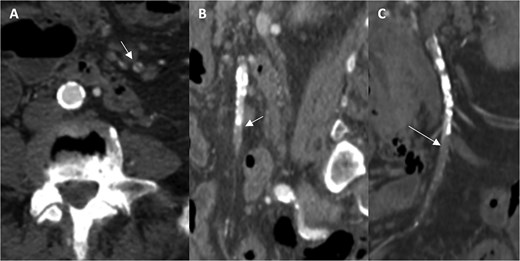

A 76-year-old female patient with a medical history of diabetes mellitus and cholecystectomy presented to the emergency department with a 7-month history of postprandial abdominal pain, food fear, and weight loss (25–30 kg). Over the past 3 days she referred symptom worsening to constant pain. On the physical examination, the abdomen was tender to palpation. Laboratory results revealed leukocytosis (13.700/μl), high C-reactive protein (23 mg/dl) and lactate 0.7 mmol/L. A previously performed computed tomography angiography (CTA) in context of a lithiasic cholecystitis revealed celiac trunk occlusion and pre-occlusive stenosis of the SMA ostium but the patient was not referred for a vascular surgery consultation. A CTA scan obtained in the emergency department revealed thrombotic occlusion of the SMA origin associated with distal embolization (Fig. 1A–C). In this context, the diagnosis of acute-on-chronic mesenteric ischemia was assumed, and the patient was proposed for urgent endovascular revascularization. A 7F (French) sheath was placed via percutaneous access in the left brachial artery, and SMA catheterization was performed using a triaxial system (sheath, MP catheter and Progreat® catheter). Diagnostic angiography confirmed the CT findings (Fig. 2A). Catheter-directed thrombolysis was first performed with a 5 ml bolus of alteplase, followed by percutaneous thrombectomy using the Penumbra® system (Fig. 2B), with retrieval of fresh thrombus (Fig. 3). Primary stenting of the SMA ostium was also performed using an Advanta® 6 × 39 mm stent with proximal flair, with an excellent imagological result (Fig. 4A and B). The postoperative course was uneventful, with significant improvement of symptoms and clinical status. A CTA prior to discharge revealed a patent stent with proper placement and no evidence of residual thrombus (Fig. 5A and B). The patient was discharged on the seventh postoperative day with apixaban 5 mg twice daily. Follow-up of the patient at 6 months revealed that the stent remained patent, with no reported abdominal complaints. The patient gained 15 kg at this point of follow-up.

Angiographic images before (A) and after (B) thrombectomy of the superior mesenteric artery (SMA).